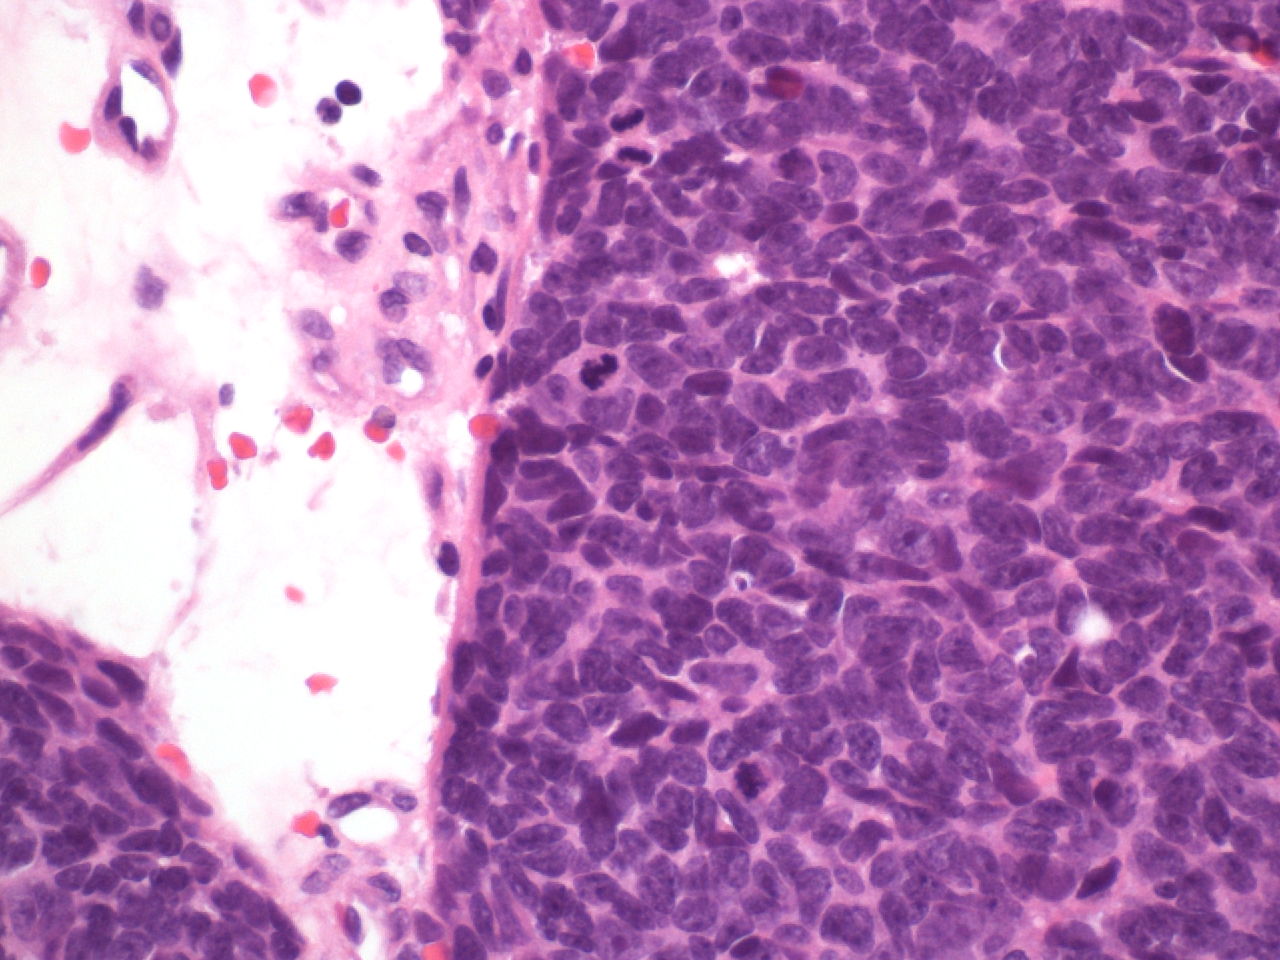

This is a biopsy of a sinonasal mass in a 58-year-old man.

Answer: C: Sinonasal undifferentiated carcinoma (SNUC)

Sections show a mitotic, small blue cell tumor without obvious squamous differentiation or rosette formation. Immunostains for p40, synaptophysin, NUT and S-100 are negative. An immunostain for low molecular weight keratin is positive and SMARCB1 is retained. Small blue cell tumors of the sinonasal tract have a broad differential diagnosis. Esthesioneuroblastoma, rhabdomyosarcoma, squamous carcinomas, small cell neuroendocrine carcinoma, melanoma, lymphoma and SNUC are the historical differential diagnosis however NUT carcinoma and SMARCB1 negative carcinomas are more recently described tumors that enter into the differential. In this case the presence of low molecular weight keratin with absence of p40, NUT and neuroendocrine markers and retained SMARCB1 leaves only a diagnosis of sinonasal undifferentiated carcinoma.